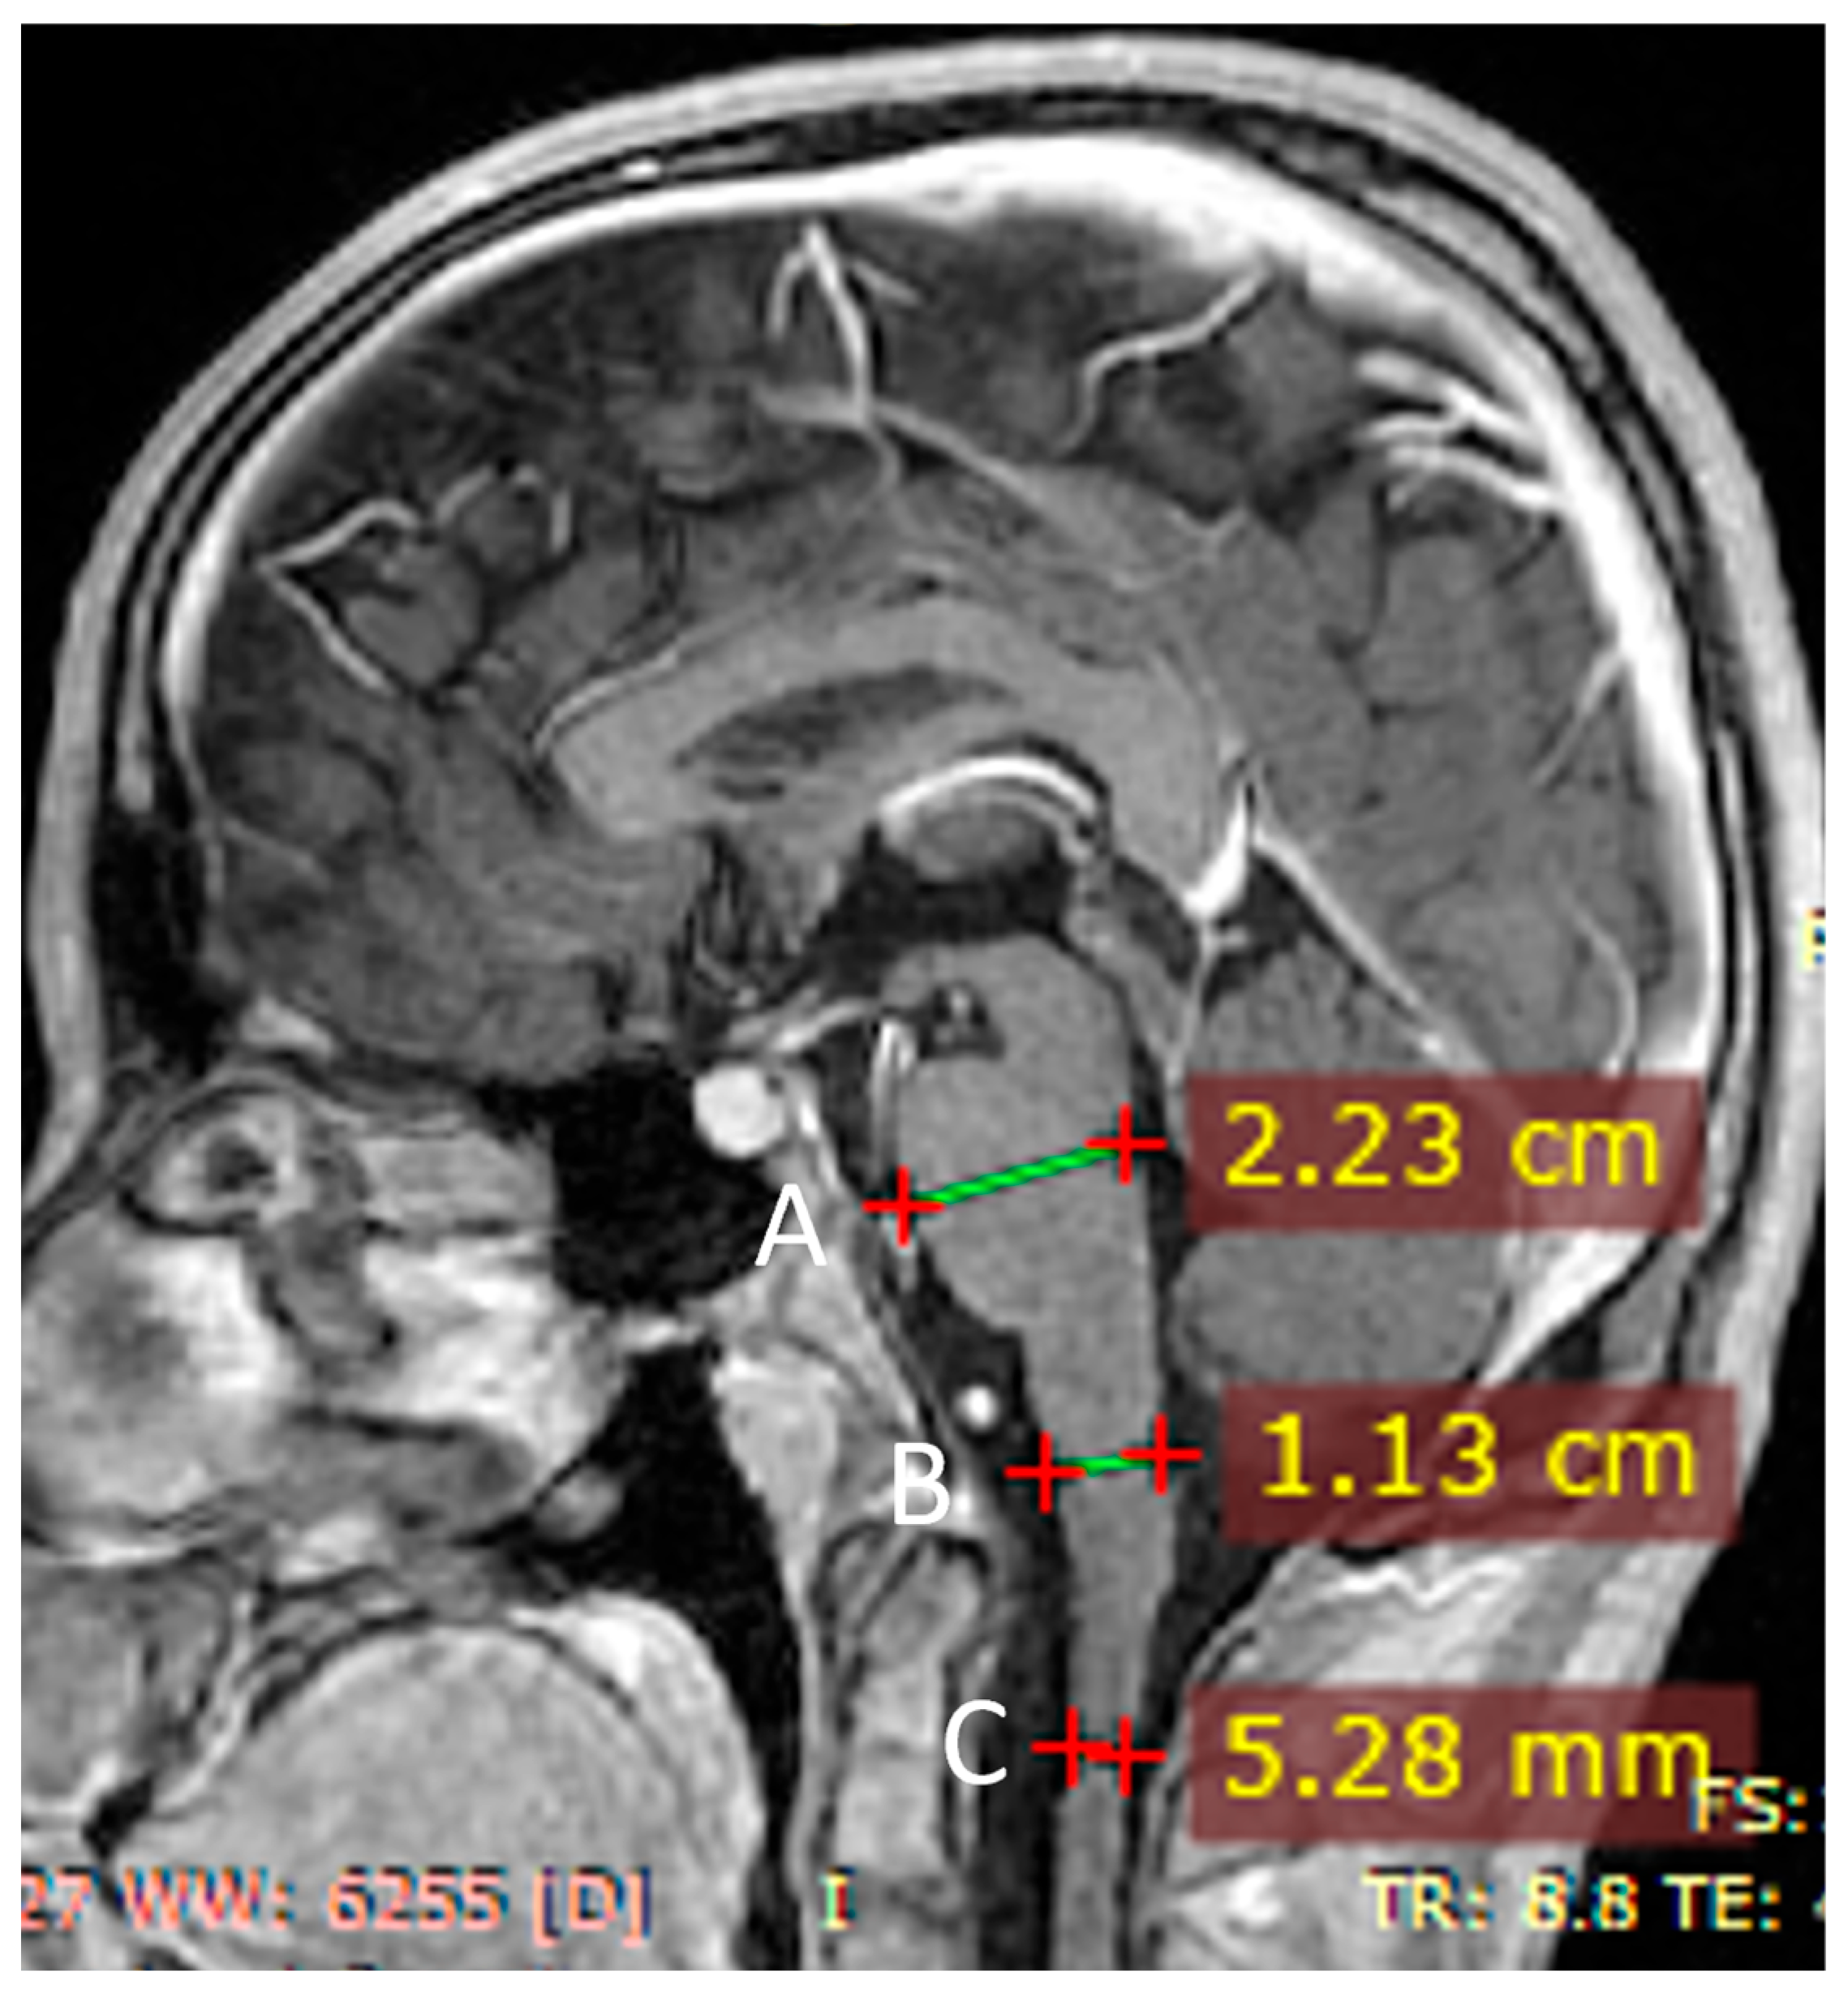

| Abnormal signal intensity of the anterior portion of the medulla oblongata | Yes | NA | Yes | Yes | Yes | Yes | Yes |

| Atrophy of the medulla | No | NA | No | Yes | Yes | Yes | Yes |

| Atrophy of the cervical spinal cord | Yes | NA | No | Yes | Yes | Yes | Yes |

- Neuroimaging characteristics